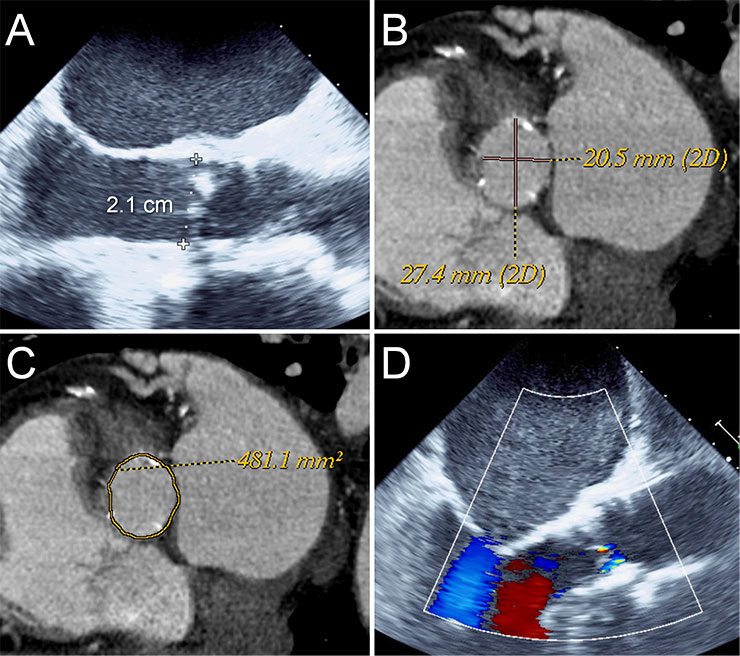

Figure 1

Annulus sizing using TEE and CT angiography. TEE measured an annulus of 2.1 cm suggesting a 23 mm Edwards Sapien or a 26 mm Medtronic CoreValve (A). CT angiography measured an area of 481 mm2 (C) and a mean diameter of 24 mm (B) suggesting a 26 mm Edwards Sapien or a 29 mm Medtronic CoreValve valve with ~10% oversizing. A 26 mm Edwards Sapien valve was implanted with trace paravalvular leak (D).